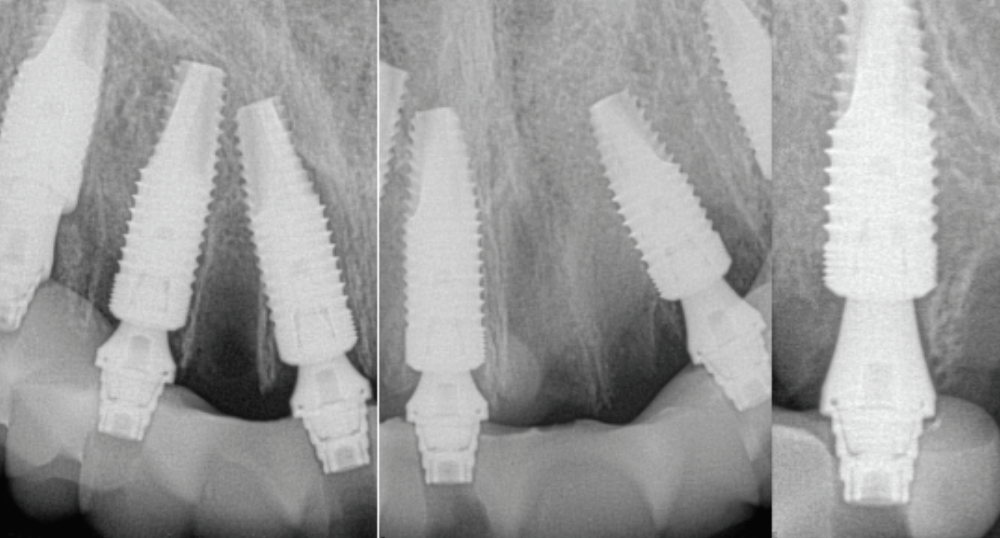

Postoperative x-rays documented the full seating of the prosthesis on the multi-unit abutments (Figure 21 and Figure 22). The patient returned at 1 week postoperatively for a follow-up visit and to review home care. She remarked that the restoration was comfortable and that she was free of discomfort and extremely pleased with the makeover she received in one day.

Fig 21. Postoperative panoramic radiograph on the day of surgery.

Figure 21

Fig 22. Postoperative periapical x-rays on the day of surgery demonstrating the provisional restoration with ti-bases fully seated to multi-unit abutments and ideal immediate implant placement.

Figure 22